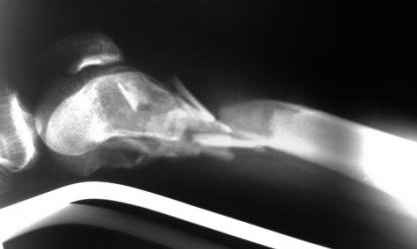

Рентгенограммы.